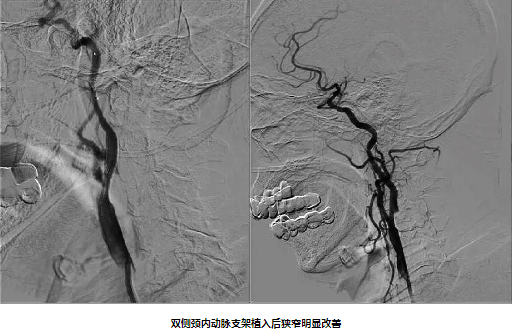

82岁男性,因“双下肢无力10天”入院,既往有“高血压病”史10年。入院后完善颈动脉彩超及影像学检查提示:1.分水岭梗死(双侧皮质下型)2.双侧颈内动脉重度狭窄 3.窦性心动过缓。经颈动脉狭窄MDT团队充分讨论,精心安排,在心血管内科中心的协助下,脑血管病专科团队克服了患者高龄、心动过缓等危险因素,成功给予患者双侧颈动脉支架同期植入,患者症状得到明显好转。